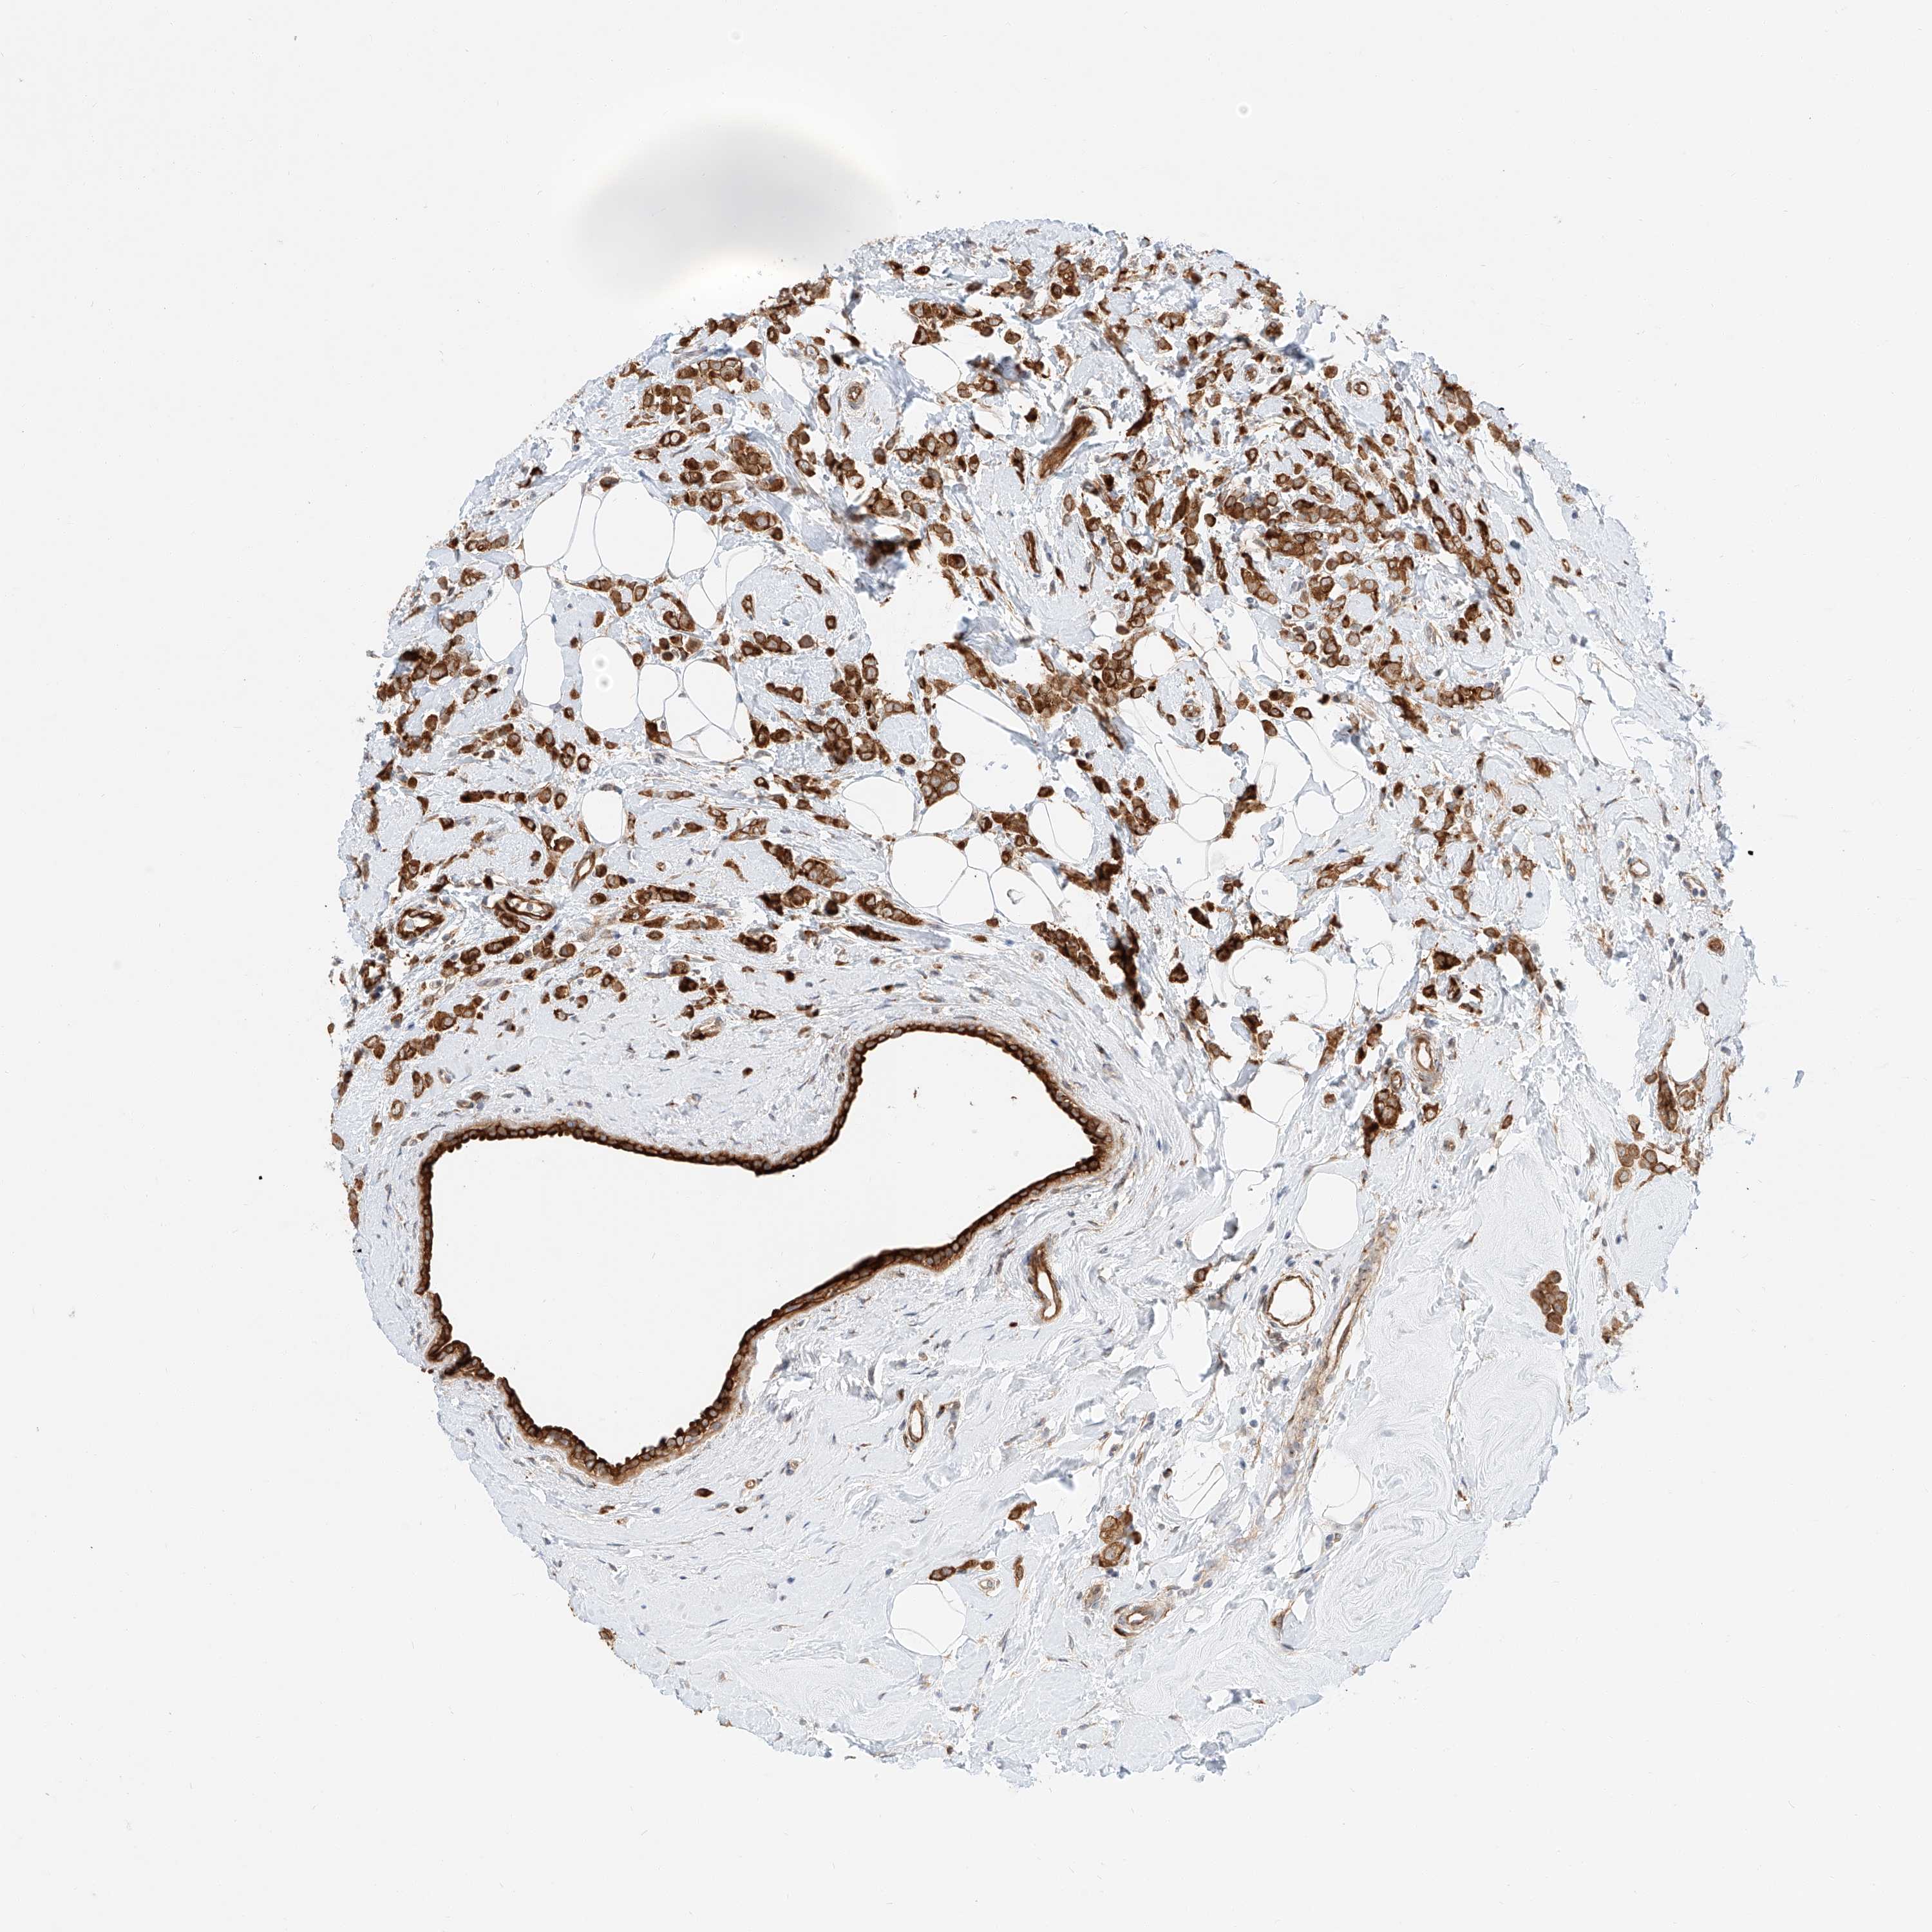

CANCER BREAST CANCER Show tissue menu

BRCA TCGA BRCA VALIDATION PROTEIN EXPRESSION